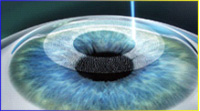

4、复位角膜瓣 完成手术 1、飞秒激光制作角膜瓣

1、飞秒激光制作角膜瓣 2、掀开角膜瓣

2、掀开角膜瓣 3、S4-IR准分子激光切削

3、S4-IR准分子激光切削 4、复位角膜瓣 完成手术

4、复位角膜瓣 完成手术